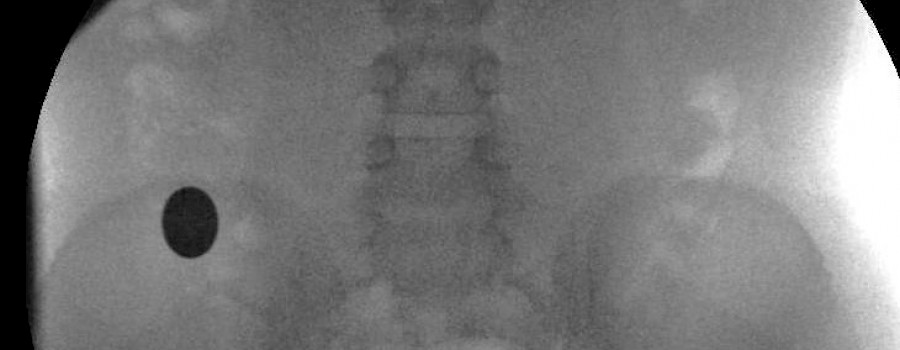

Patienten beim Röntgen halten!

Es kommt gar nicht so selten vor: Kleine Kinder, Behinderte oder demente Patienten, die einfach nicht in der Lage sind, trotz diverser Lagerungshilfen, das aufzunehmende Körperteil ruhig zu halten!